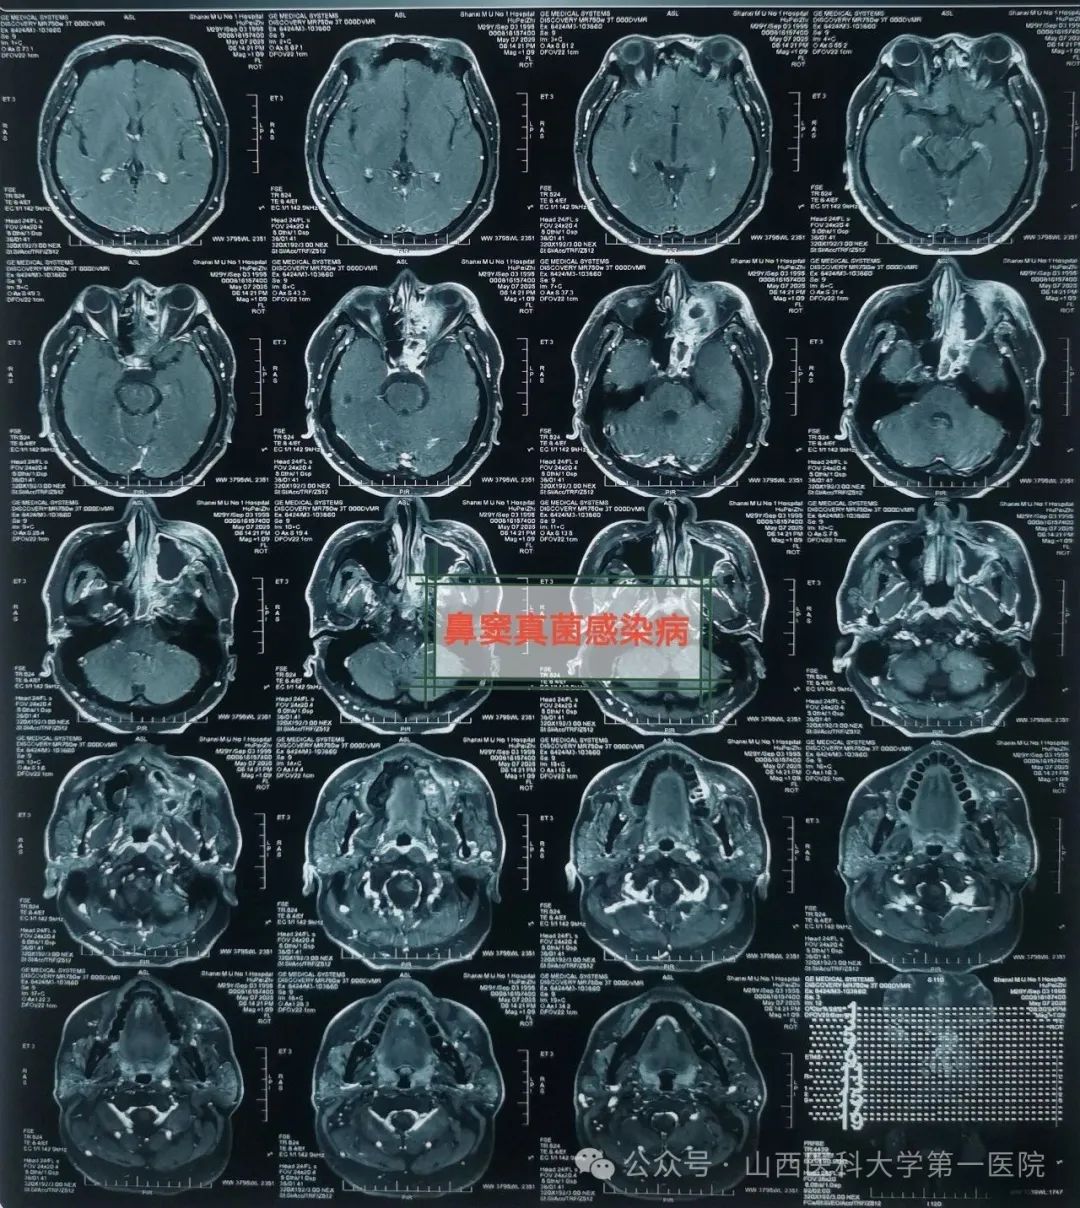

49岁的袁先生过敏性鼻炎多年,合并糖尿病与痛风,一直药物维持治疗;2年前因合并鼻窦炎,口服药物治疗效果不佳;近数月以来病情逐渐加重,鼻塞流涕,最近头痛头闷症状越来越严重同时出现鼻涕带血丝,就诊于东京热

耳鼻咽喉-头颈外科,确诊为鼻窦真菌感染,医生通过手术切除鼻腔病变组织,清除霉菌团块,开放鼻窦,引流分泌物,清洗术腔,重建鼻腔结构、恢复功能,改善并缓解了临床症状。

耳鼻咽喉-头颈外科皇甫辉教授介绍,真菌性鼻窦炎是临床常见的特异性感染性疾病,近年来发病率有上升趋势,可能与抗生素广泛使用、环境污染等有关,而糖尿病、抗肿瘤药物治疗、放疗以及长期使用激素等是真菌性鼻窦炎的高发人群。真菌性鼻窦炎通常分非侵袭型真菌性鼻-鼻窦炎与侵袭型真菌性鼻-鼻窦炎两类,非侵袭型真菌性鼻-鼻窦炎之病变局限在鼻窦腔内,粘膜和骨壁内却无真菌侵犯;而侵袭型真菌性鼻-真窦炎是真菌感染不仅位于鼻腔,同时侵犯鼻窦粘膜和骨壁,并向鼻窦外周围结构和组织如眼眶、前颅底或翼腭窝等侵袭发展,一般情况下,侵袭型真菌性鼻-真窦炎预后凶险。

皇甫辉讲到,低免疫功能、低氧及高血糖环境是真菌生存合适条件,局部因素也是部分真菌性鼻窦炎主要致病因素之一,各因素所致鼻腔鼻窦通气引流受阻,解剖因素如中鼻道狭窄、中鼻甲反向偏曲等,局部炎症水肿,窦腔分泌物潴留,同侧上列牙齿病变等。真菌性鼻-鼻窦炎侵袭型者一经确诊,应尽早手术,清除鼻腔和鼻窦内真菌病原和坏死及不可逆之病变组织,恢复鼻腔鼻窦通畅引流,病变范围广者可采用柯-陆氏手术、与鼻内镜手术联合等术式,病变累及颅内时可采用颅面联合术式,术前应用抗真菌药物治疗,术后可应用抗真菌药物冲洗鼻腔和鼻窦等。